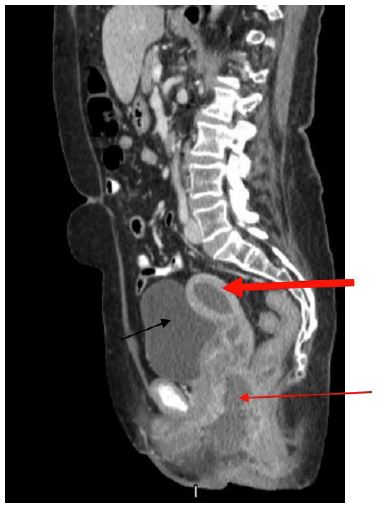

The patient represented on POD 18 again with fever and worsening perineal pain. She was febrile, white blood cell count was elevated, and CT showed a similar fluid collection in the uterus and re-accumulation of the perineal abscess (Figure 2). She was admitted for antibiotic administration and interventional radiology was consulted for drainage of the two areas of abscesses. On POD 19, a drain was placed vaginally into the uterus as well as a second drain into the perineal collection (Figures 3 & 4). The cultures ultimately revealed multidrug resistant Escherichia coli and Enterococcus raffinosus. She was subsequently treated with Meropenum. The patient improved and was discharged home on POD 27 without any further treatment necessary.

Figure 3: Drain placed by Interventional Radiology under CT-guidance into the uterine as shown by a short red arrow. The drain shows up bright on this image. Visible portions of the drain within the abscess tract are pointed out by the long red arrow. The bladder is shown by the thick black arrow.